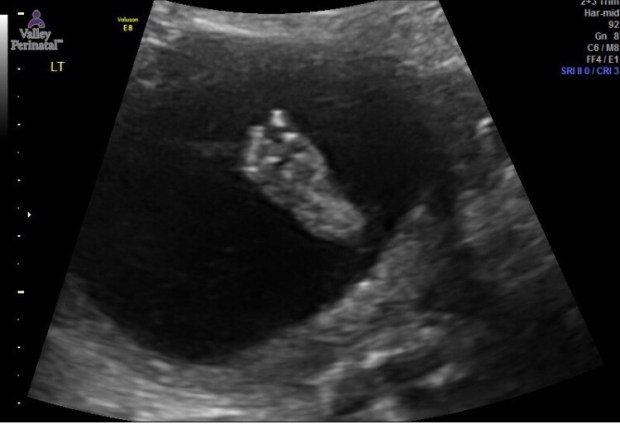

At the ultrasound, we first checked on our baby’s health and were relieved when told everything was looking healthy. We heard our baby’s fast heartbeat and saw her move around playfully. It was actually pretty cute; she would move her hands around and even looked up at us for a second, long enough for us to “oooh” and “aaaa” about it.

The last thing we looked at was our baby’s gender. It was pretty obvious to hubs and I that it was a girl from the very beginning of the ultrasound. We glanced at each other and whispered “girl” but we still hadn’t officially heard the words so we had to wait anxiously. Finally, when we were told it was a girl, I completely and unexpectedly balled my eyes out. The sonologist kept asking “Do you see it, do you see what I am looking at” and I just couldn’t speak…only cry! I had the happy ugly cry look all over my face and I just couldn’t help it! I glanced over at hubs and he looked so confused…HA…sorry hubs, emotional preggo over here!